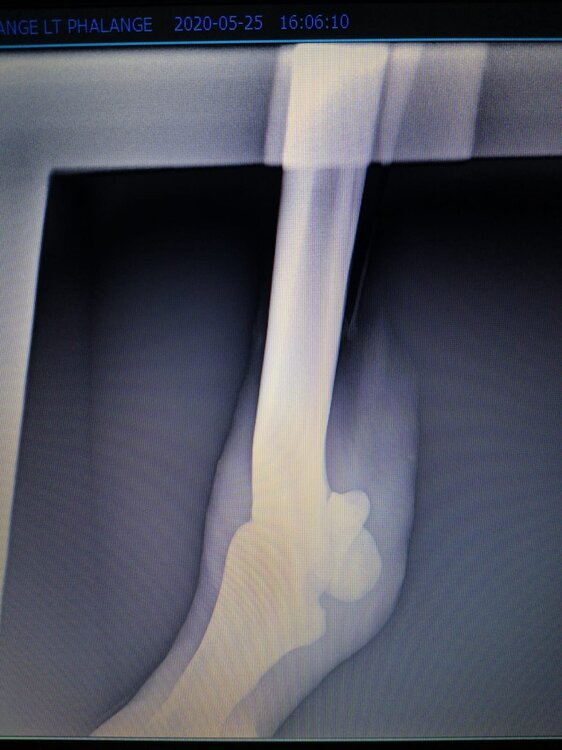

Salve volevo chiedervi qualche informazione in merce tò a un problema che ho avuto con la mia puledra. Qualche settimana fa mentre stavo lavorando alla corda è scivolata urtato l'arto posteriore sinistro. Arrivati in box ho messo dell'acqua a pressione perché si era gonfiato sia il nodello sia il pastorale. Già l'indomani l'arto era sgonfio ritornato normale, quindi ho continuato a lavorarla. Ma dopo qualche giorno di lavoro alla corda leggerissimo, al rientro in box ho notato che sia il nodello che il posturale gonfiavano nuovamente. Allora ho chiamato il veterinario che ha detto che la cavalla aveva una lussazione e mi ha insegnato come cura una fasciatura con della creta per 24h per cinque giorni e un antinfiammatorio. Dopo un paio di giorni la fasciatura ha fatto come delle vesciche e il gonfiore è aumentato dal pastorale alla garra. Abbiamo chiamato un altro veterinario abbiamo fatto vedere anche a lui la cavalla e diceva che poteva essere la frattura del ditino, ma si dovevano fare le lastre per essere sicuri. Ora abbiamo fatto le lastre e il radiologo dice che c'è dell'infiammazione ma non c'è niente di grave. Il veterinario,viste le lastre dice che deve essere operata. Allora abbiamo consultato un'altro veterinario che dice che la cavalla non ha assolutamente niente. Ora io vi allego le radiografie, datemi un vostro parere perché non só più cosa fare. Grazie